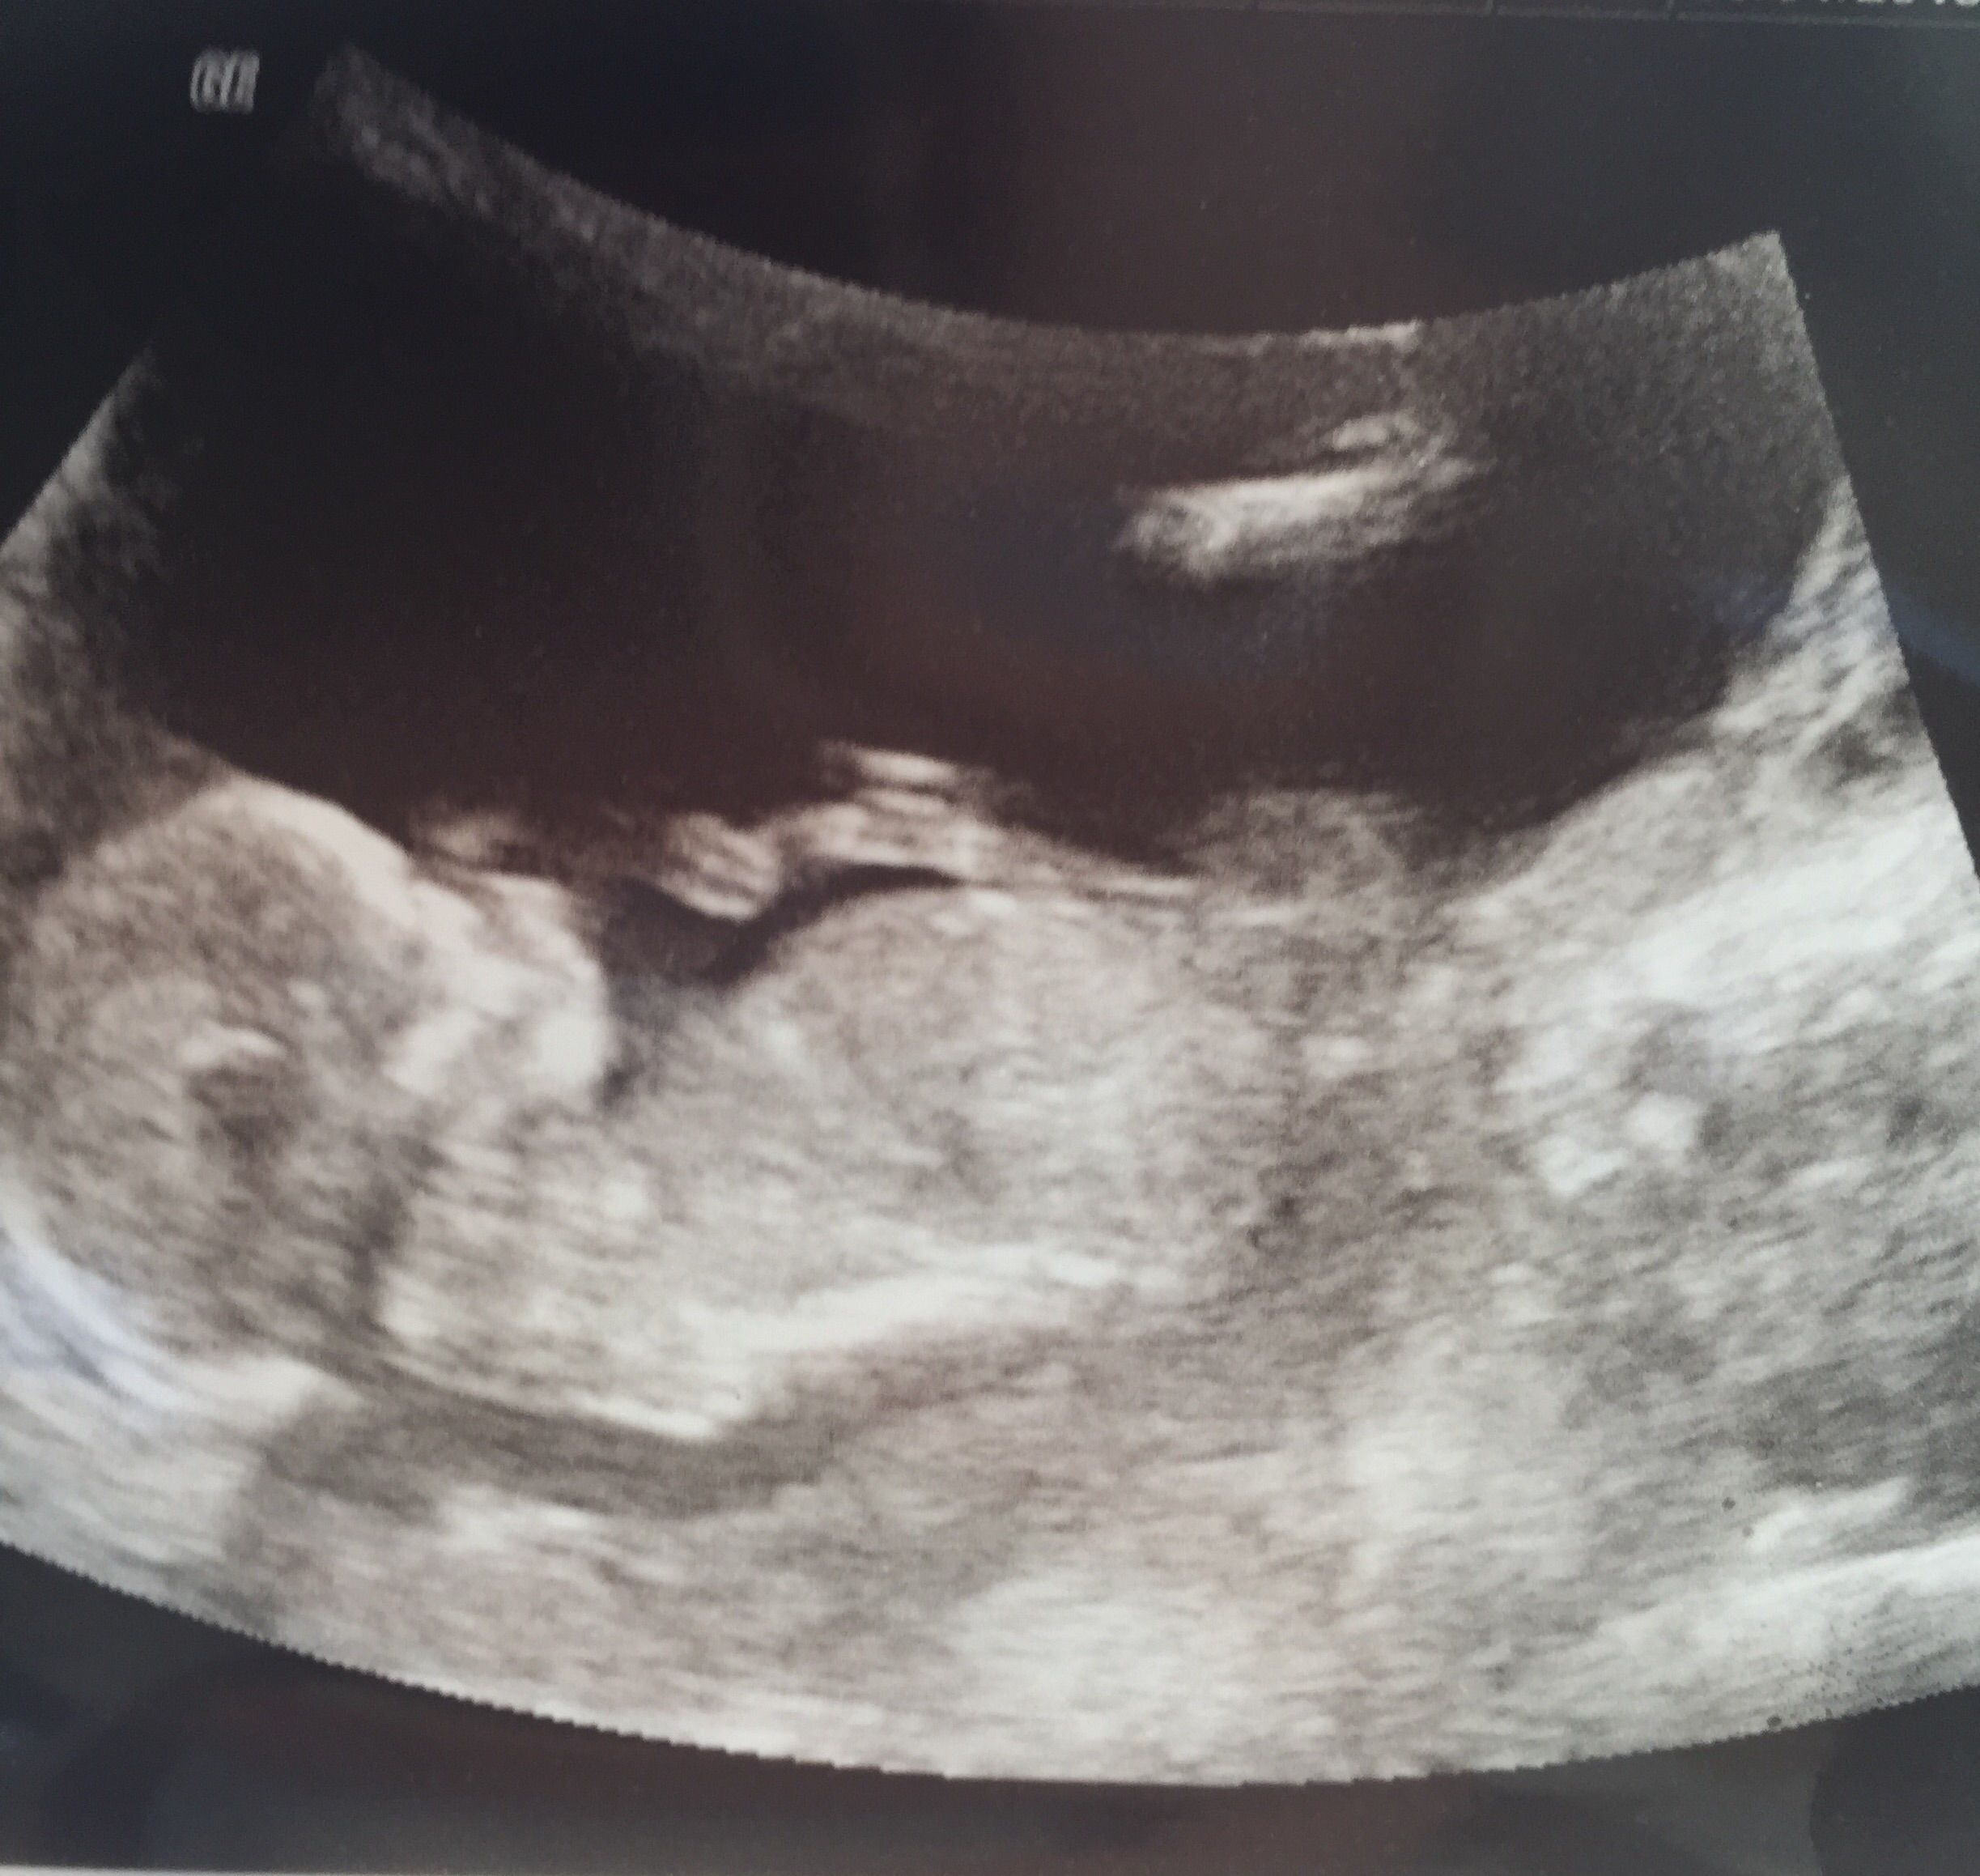

I'm jealous of everyone's great shots. I've decided this little one is not photogenic. The pictures are horrible but lo was moving like crazy today, so that's good. Anyone else's look squished already? 12w5d at my scan today. Might be the angle.